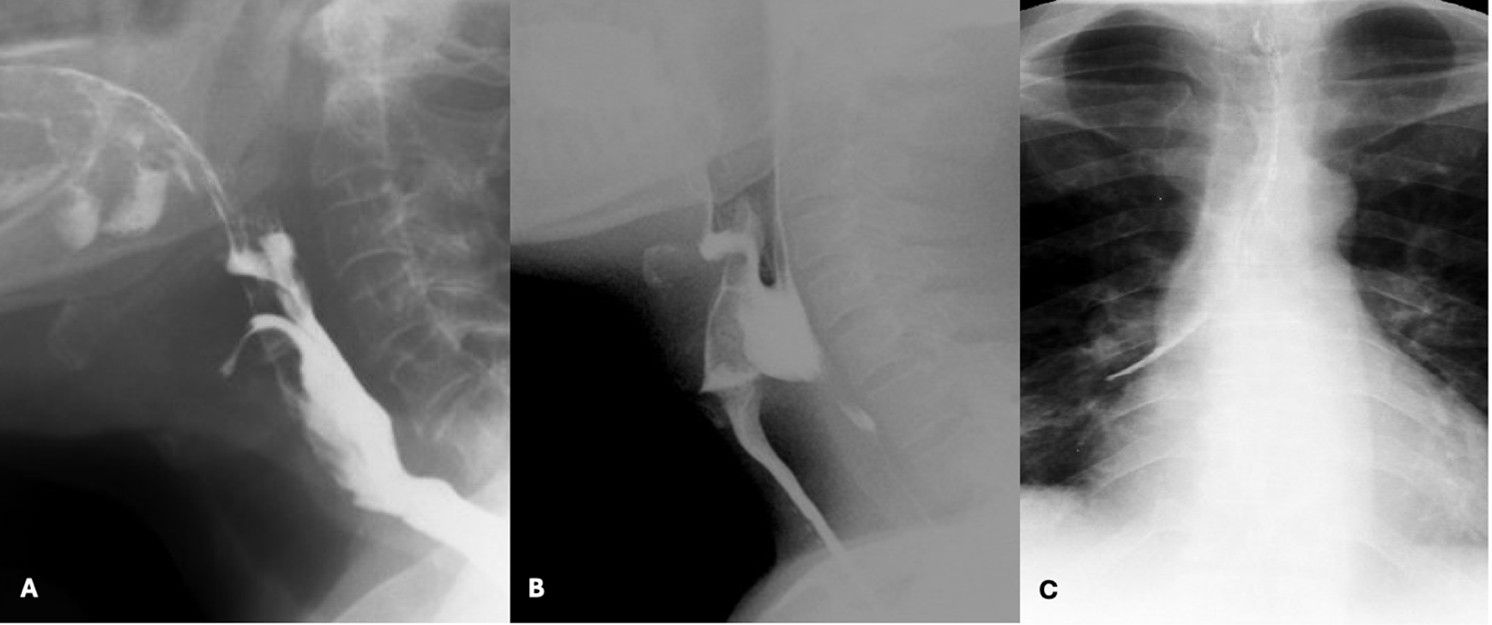

When food enters the airway, different degrees of severity can be observed: the term penetration is used when boluses enter the larynx but remain above the vocal folds, while aspiration is used when they pass below this level. Usually, we grade the subjective amount of contrast that accesses the airway, state whether a cough response was triggered (i.e. if silent aspiration is present or not) and if there is effective clearance of contrast from the airway. A more objective assessment can also be employed by using the Penetration-Aspiration Scale developed by Rosenbek et al.29 (Fig. 10)

Figure 10: Spectrum of airway protection impairment severity - penetration (A), aspiration (B) and aspiration that reaches the right main bronchus (C)

Penetration and aspiration can be classified according to the timing of their occurrence, which helps to identify the underlying causal mechanism. When there is incomplete closure of the larynx or delayed triggering of the swallow reflex, contrast enters the airway during the pharyngeal phase of deglutition. Aspiration can also occur before the pharyngeal phase of deglutition, typically in the setting of posterior escape from the oral cavity or poor coordination in oropharyngeal bolus transport. On the other hand, aspiration can also occur after the pharyngeal phase of deglutition when there are persistent pharyngeal residues that can spill into the airway when the larynx opens - this occurs when pharyngeal clearance is hindered by insufficient contraction of pharyngeal muscles, incomplete opening of the upper oesophageal sphincter or presence of obstructive masses. (Fig. 11)

Figure 11: Range of underlying causes for compromised airway protection. (A) Posterior bolus escape from the oral cavity resulting in laryngeal penetration before the pharyngeal phase of deglutition; (B) Aspiration of contrast during the pharyngeal phase of deglutition due to delayed triggering of the swallow reflex; (C) Persistent pharyngeal residues that resulted in the aspiration seen in the panel B of figure 10